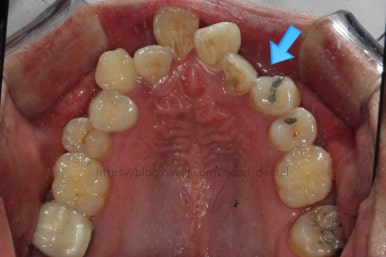

파노라마 X-ray 사진 입니다.

사랑니가 굉장히 위쪽으로 묻혀 있어요. 이렇게 묻혀 있는 사랑니는 사실상 그냥 놔둬도 괜찮아요.

과잉치가 보이네요. 앞니 사이에 과잉치는 굉장히 빈번한데 주위 치아에 안좋은 영향을 줄 때는 뽑는게 좋아요. 이번 환자분은 뽑기로 했어요.

입 안에서 보이지 않던 송곳니가 여기 있었네요. 송곳니는 굉장히 중요한 치아라서 왠만하면 살려 쓰는게 가장 좋긴한데요. 위치랑 다른치아와의 관계 등을 고려해서 뽑을지, 꺼내쓸 지를 결정해야 돼요.

송곳니 부위를 좀 더 정밀하게 CT 사진을 찍었어요.

매복치아를 꺼낼 수 있는 기능성, 주위치아가 오히려 손상 받지 않을지, 총 치료기간 등을 고려했을 때 이번에는 발치하기로 결정했어요.

돌출입을 개선할 때 일반적으로 작은 어금니를 발치교정 하는데, 이번의 경우 작은 어금니 대신 송곳니를 발치했다고 치면 되니까요.

매복치아를 꺼내서 쓸 수만 있다면 꺼내는게 가장 좋으나 이번의 경우는 아니였던 거지요.